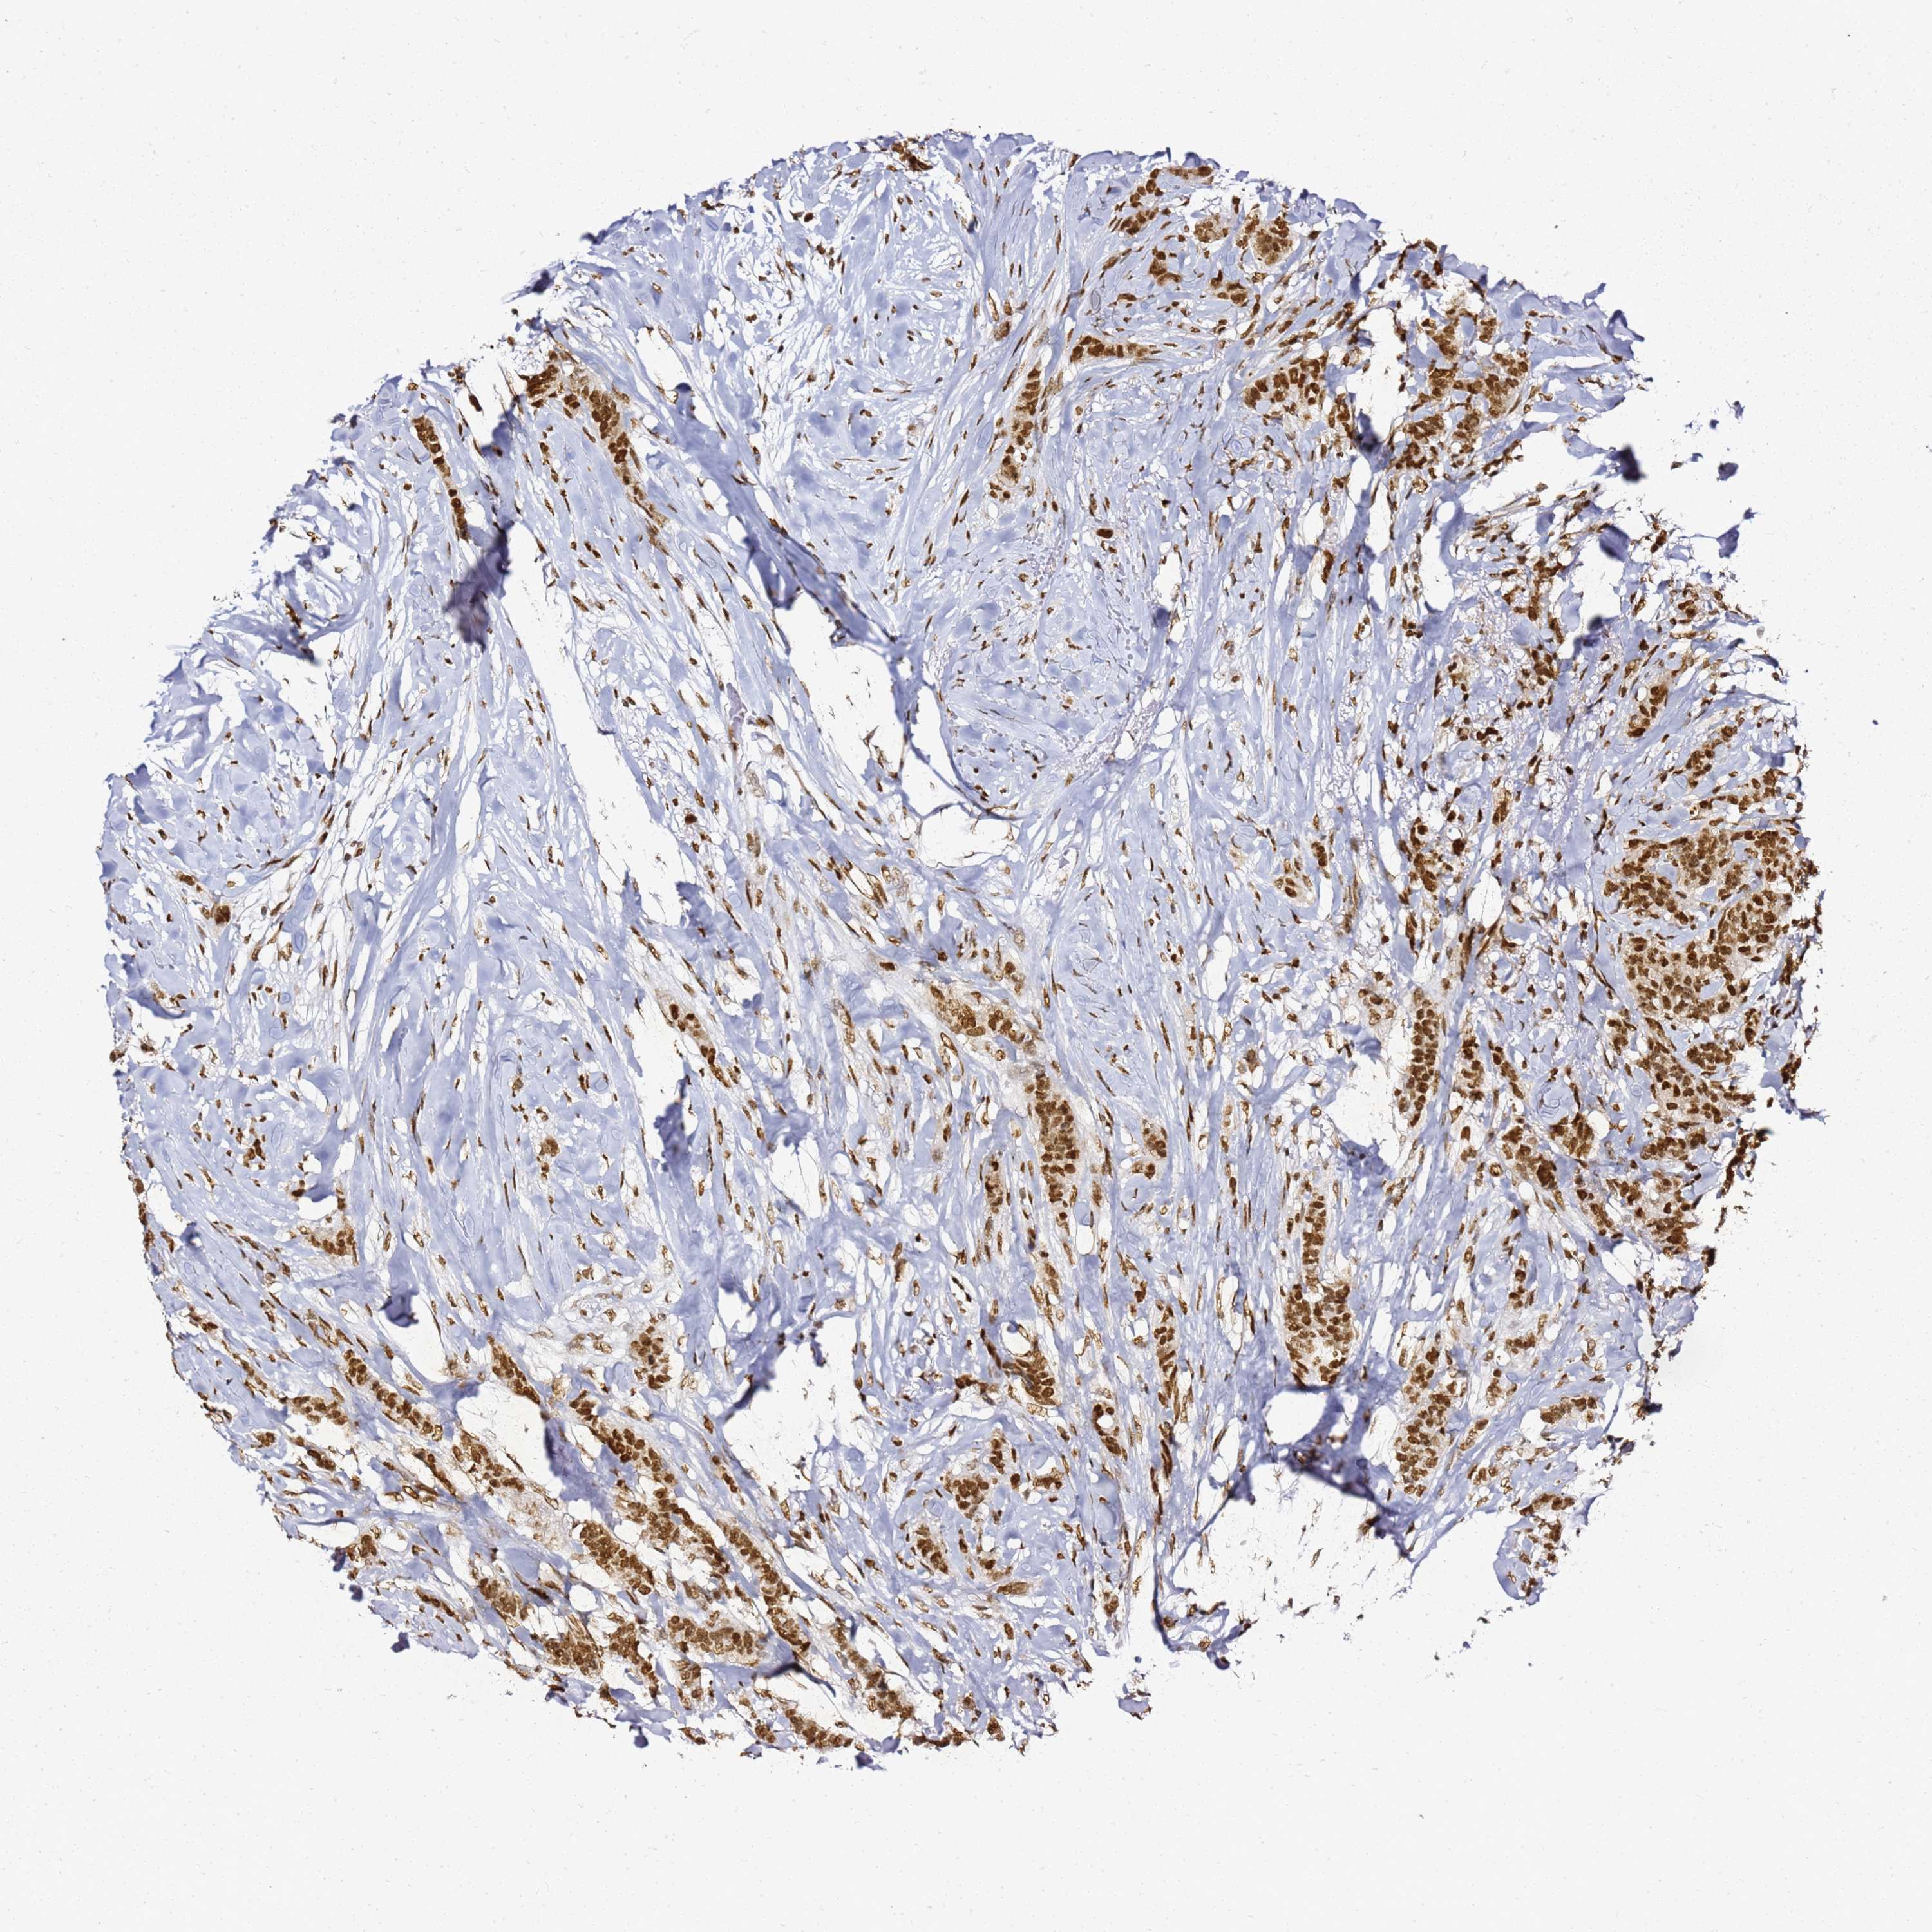

CANCER BREAST CANCER Show tissue menu

BRCA TCGA BRCA VALIDATION PROTEIN EXPRESSION

ANTIBODIES

AND

VALIDATION